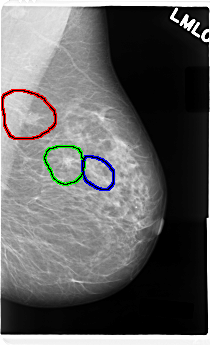

C_0087_1.LEFT_MLO

FILE: C_0087_1.LEFT_MLO.OVERLAY

TOTAL_ABNORMALITIES 3

ABNORMALITY 1

LESION_TYPE CALCIFICATION TYPE PLEOMORPHIC DISTRIBUTION CLUSTERED

ASSESSMENT 5

SUBTLETY 5

PATHOLOGY MALIGNANT

TOTAL_OUTLINES 1

BOUNDARY

ABNORMALITY 2

ABNORMALITY 3